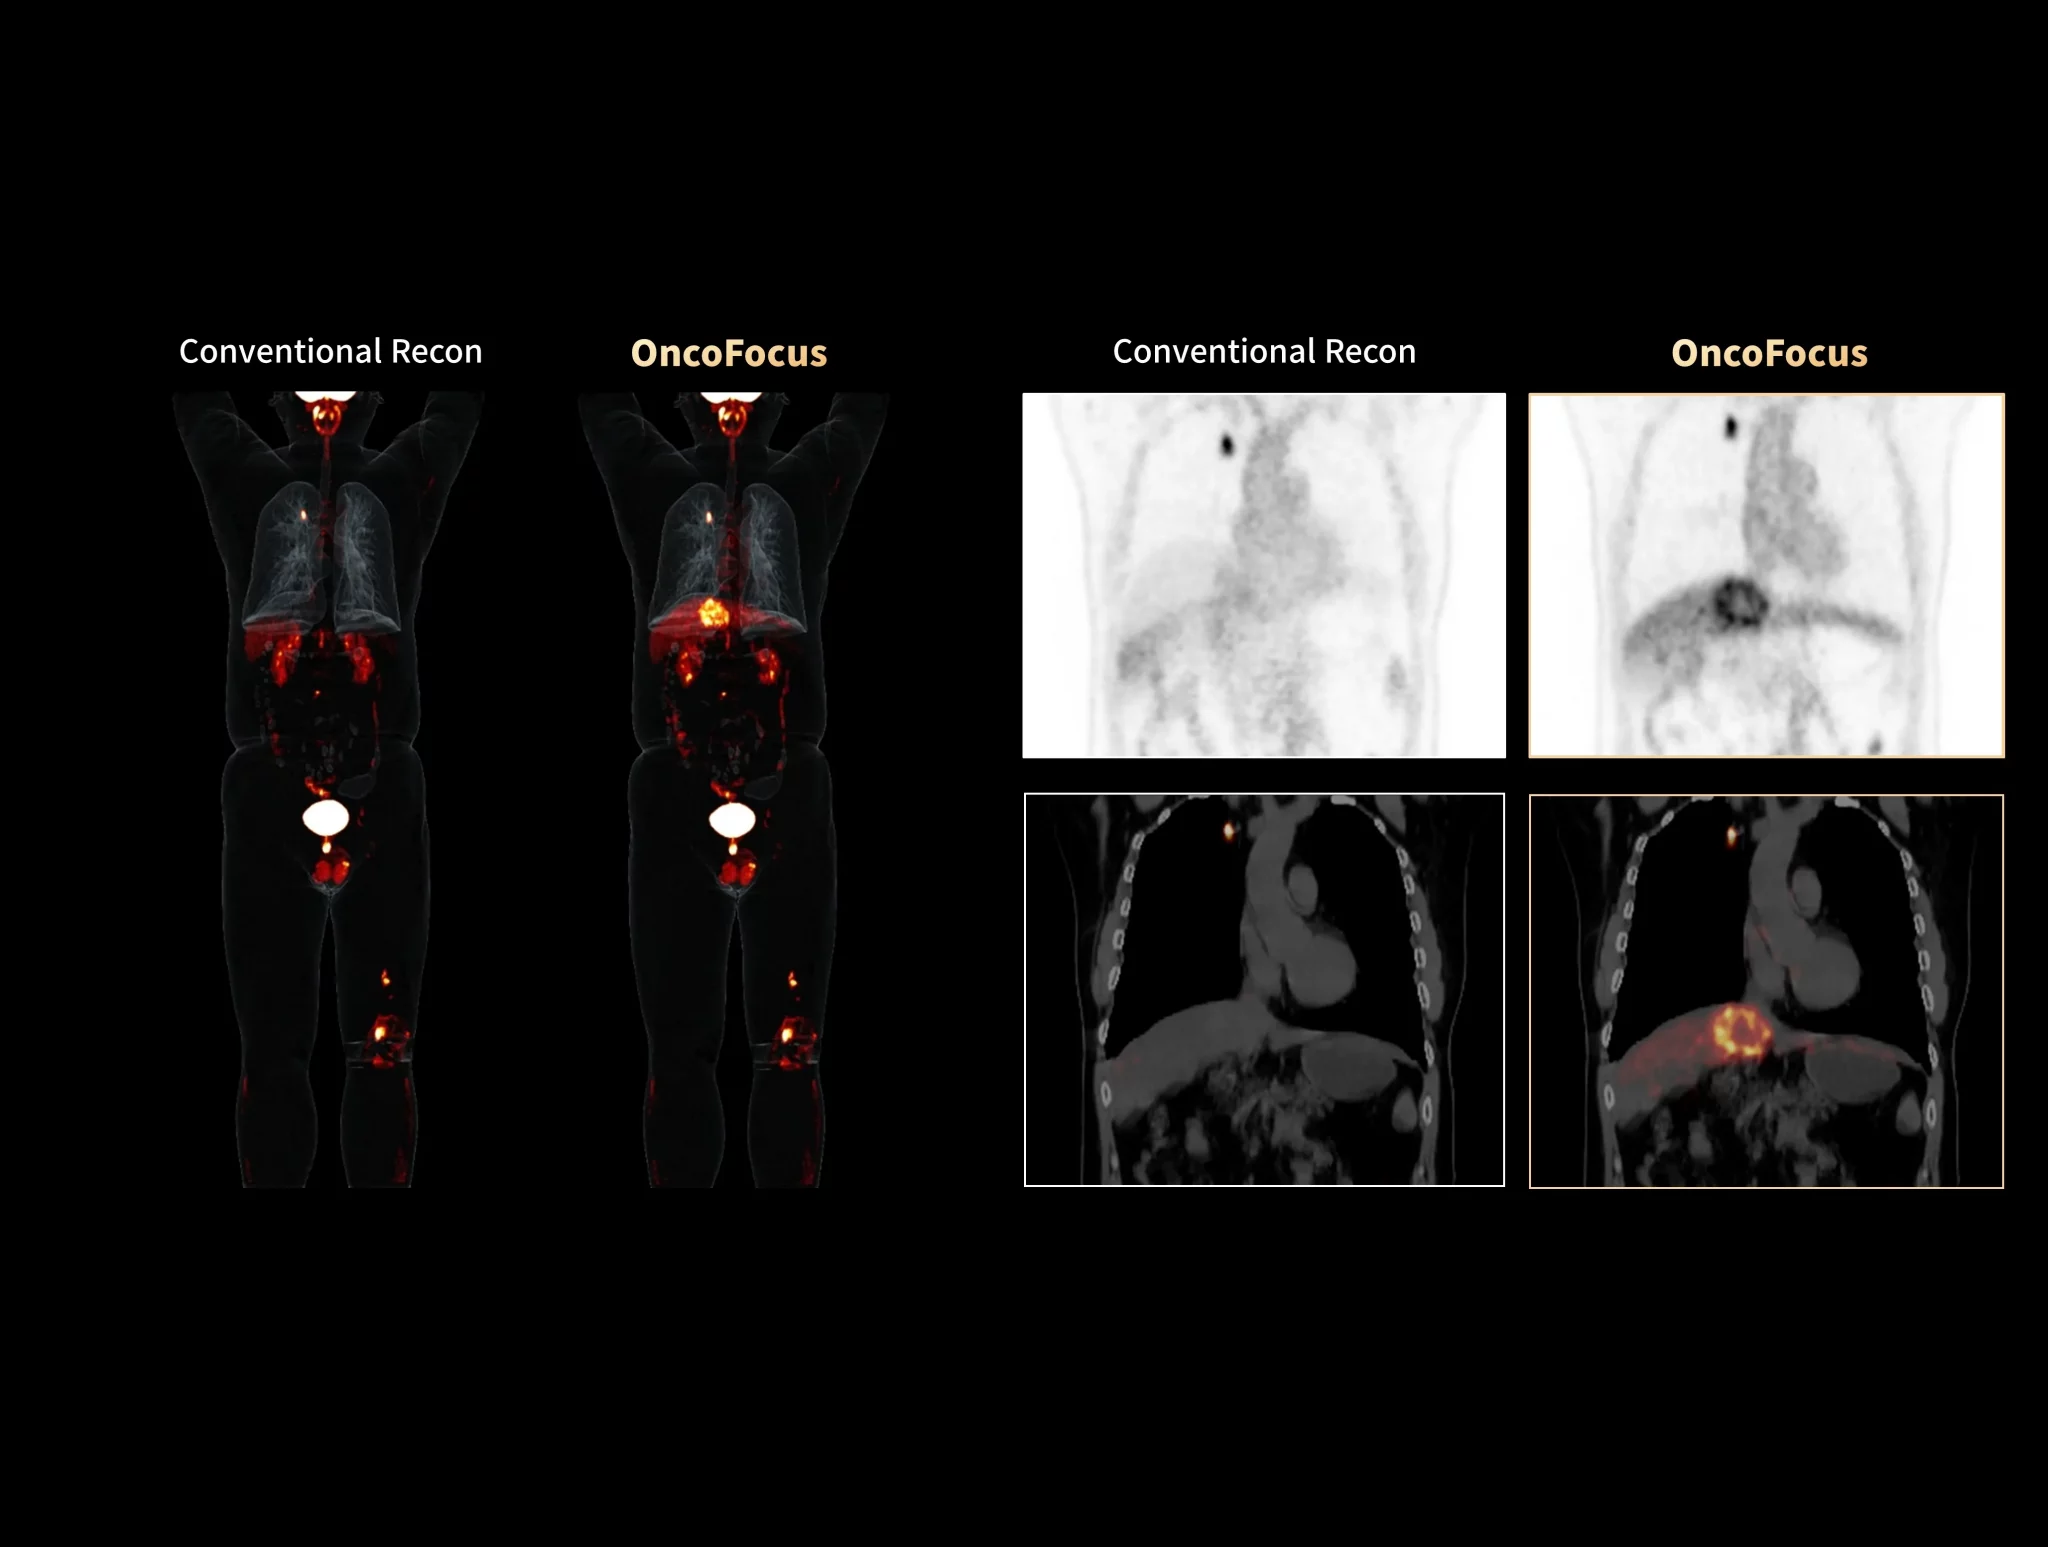

uMI Panorama is greatly empowered by innovative technologies integrated into the uExcel SCAN and uExcel CARE workflows. With uExcel SCAN, you can rely on intelligent positioning, scanning, and motion correction to streamline your routine tasks and maximinze your work efficiency. And uExcel CARE features uExcel DPR and uExcel AIIR reconstruction algorithms to ensure clear images even at low doses.

Unlock New Possibilities for Exploration

With the ultra-high system performance, uMI Panorama faces up to the challenges of tracers with different half lives and the complex scanning conditions, without compromise for image quality.